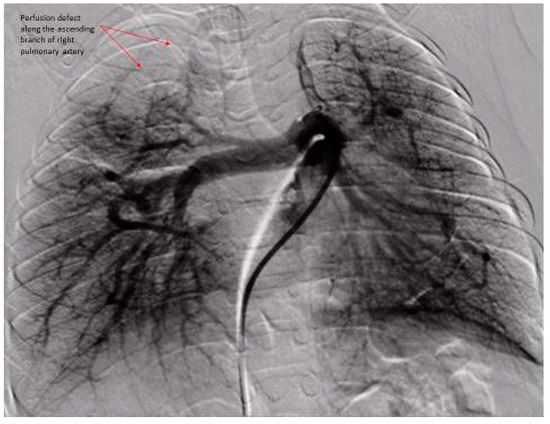

- Das, B.B.; Jadotte, M.M.; Mills, J.; Chan, K.C. Digital subtraction pulmonary angiography in children with pulmonary hypertension due to bronchopulmonary dysplasia. Med. Sci. 2019, 7, 26. [Google Scholar] [CrossRef] [PubMed]

| Pulmonary Vascular Underperfusion Score (PVUS) a (mean ± SD) | 2.66 ± 0.47 | 5 ± 0.81 | 0.0048 |